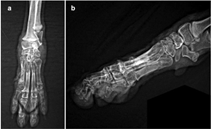

The management of metacarpal fractures can be either conservative, following a closed reduction and coaptation approach, or surgical where multiple techniques have been described including either internal or external fixation or a combination of both.6,7 To date, there is no consensus in the veterinary literature on which approach should be preferred.3 but general considerations when deciding the approach include the age of the animal, the type of the fractures, the extend of the bone and soft tissue damage, whether the fractures are open or closed, the presence of infection in old fractures and the concurrent presence of fractures in neighbouring bones.3‒6 In this case the closed reduction and coaptation technique was elected, as described by various authors for single or dual metacarpal fractures.4‒8 but modified due to fractures present on all metacarpals (Figure 1). The animal was placed on Sternal recumbency under deep anaesthesia. An Allis tissue forceps was placed on the nail of the 2nd digit and one on the nail of the 4th digit and the ends of the forceps were tied to a steady point on the wall via a traction rope in order to achieve better distribution of the traction force on all digits, whilst making certain that the limb and rope are on a straight line and exactly parallel to the table surface. Gentle and steady distal-to-proximal traction was applied on the limb with the surgeon’s left hand placed right proximally to the carpus while the right hand applied lateral-to-medial pressure on the metacarpal area in order to achieve axonal alignment. Under traction, a modified Robert-Jones splint was applied to provide stabilization. Postoperative radiographs showed good fracture reduction and alignment (Photo 2). Very strict rest was advised for 7days postoperatively and pain management was continued at home with carprofen at 4mg/kg orally once daily for 18 days. Gradual increase in exercise was advised after day 7 to encourage use of the limb and assist fracture healing. The splint was inspected on the 3rd and 12th day postoperatively for any signs of dressing complications such as vascular compromise of the limb or pressure-dermatitis, with no signs of complications. Conscious radiographs taken 18days postoperatively (Photo 3) revealed healing of the fractures and the animal was confident in using the limb with no indication of lameness. The splint was removed at day 20 and a small course of physiotherapy was followed for 2weeks due to moderate postoperative muscle atrophy. Follow-ups at 6 weeks and 3months after reduction, confirmed full recovery and return to normal activity.

Photo 3 Postoperative radiographs 18years after closed reduction. Dorsopalmar (a) and lateral (b) projections.